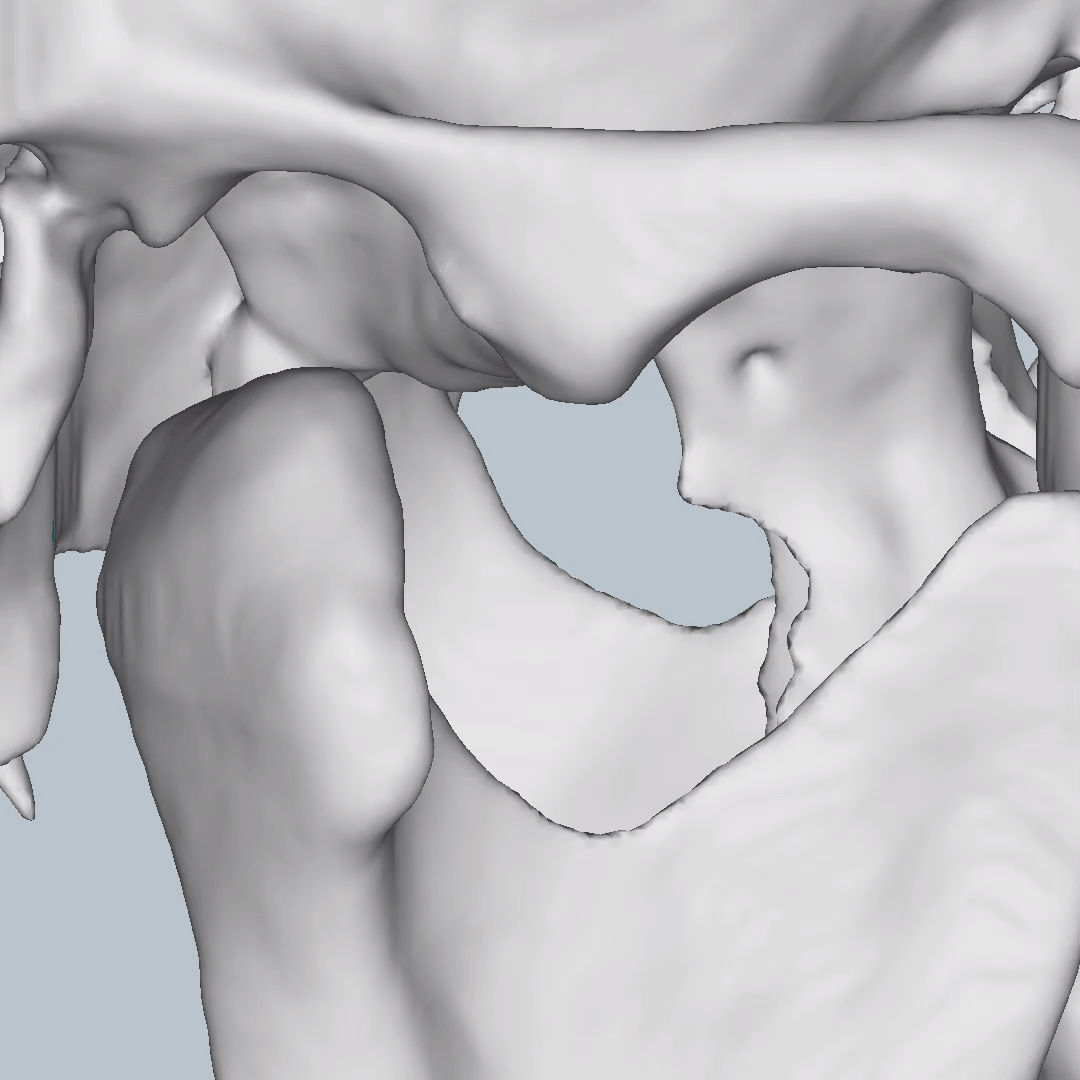

This is one feature that actually made Diagnocat very popular early on. It was the only software that made CBCT segmentation easy. Nowadays, there are several different companies and software that carry out segmentation. Diagnocat was the first and is still arguably the best at it.

So what is Segmentation? It basically means taking the CBCT and delineating all the different 3D structures, bones, individual teeth, etc.

These can then be individually exported via the software by generating STL files from CBCT dicom data. This can be used in other dental software. Jaw STLs can be used in Modjaw (jaw motion capture) for TMJ analysis, for example. As well as in exocad to help visualize the jaws for surgical planning or guide creation.

- CBCT segmentation

STLs of upper and lower jaws imported into Modjaw for TMJ analysis in jaw motion. this is made possible by CBCT segmentation using Diagnocat.

The surgical crown lengthening guide was made with the aid of maxilla STL to visualize crestal bone level. Again thanks to CBCT segmentation by Diagnocat.

CBCT Segmentation into STL

Generate STL files from CBCT DICOM data.

Generate maxilla and mandible in one STL file or face, teeth, maxilla, mandible, airway, cranial base, canals as separate STL files.